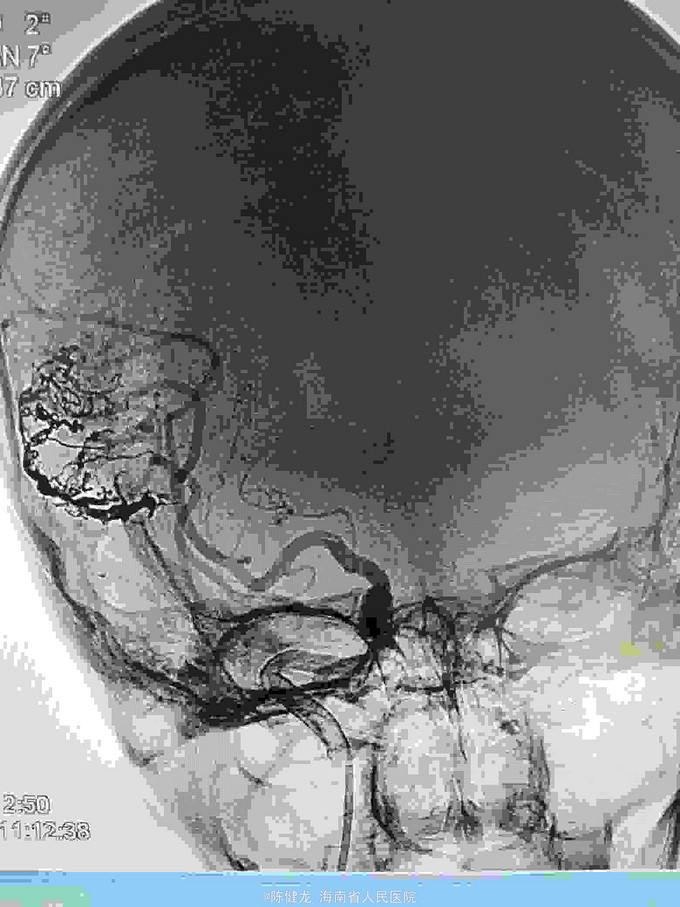

AVM

右颞大型AVM,大脑中主要供血。

右颞AVM

己进行二次治疗,拟近期内进行第三次治疗。争取80%至90%栓塞,残留部分伽玛刀治疗。